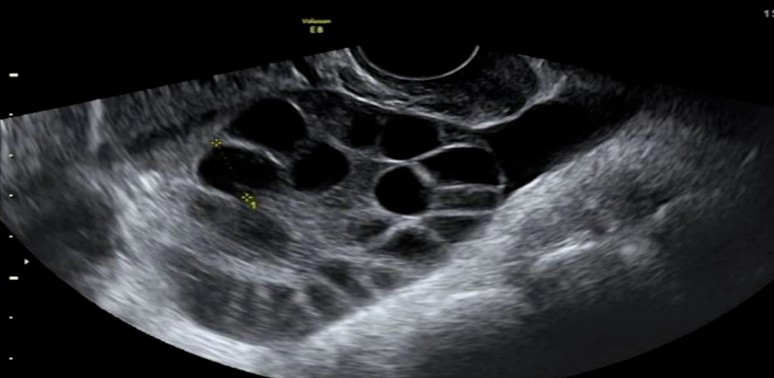

卵巢功能好坏,当然是影响自然怀孕和试管婴儿成功的重要因素。传统上用来预测卵巢中卵泡库存量的指标有:女性年龄、窦卵泡数、经期第2-3天性激素六项中的FSH、LH及E2。

AMH的临床应用还包括:在试管婴儿疗程中,是医生评估促排卵用药方法和剂量的重要参考,亦可评估发生卵巢过度刺激的风险,对多囊卵巢综合征的诊断亦有决定性的参考价值。